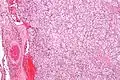

| Micrograph of a carotid body tumor (a type of paraganglioma). | |

The paragangliomas appear grossly as sharply circumscribed polypoid masses and they have a firm to rubbery consistency. They are highly vascular tumors and may have a deep red color.

On microscopic inspection, the tumor cells are readily recognized. Individual tumor cells are polygonal to oval and are arranged in distinctive cell balls, called Zellballen.[8] These cell balls are separated by fibrovascular stroma and surrounded by sustentacular cells.

Micrograph of a carotid body tumor